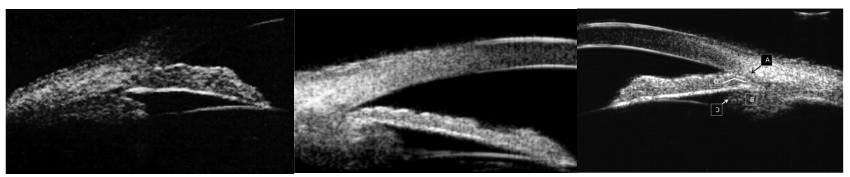

原发性闭角型青光眼(PACG)根据房角关闭的机制可分为瞳孔阻滞(PB 38.1%)、非瞳孔阻滞(nPB 7.1%)和多种机制共存(54.8%)(见图1)。手术干预房角关闭降低眼压的机制主要为纠正房角关闭(晶状体摘除、房角分离、睫状体成形)、增加房水流出(小梁切除手术、小梁切开手术等)、减少房水产生(睫状体光凝)。以往滤过手术不能提供稳定的屈光,较易出现切口出血、浅前房、脉络膜脱离、滤过泡渗漏和感染等并发症,且单独白内障超声乳化(Phaco)因只纠正晶状体导致的房角关闭,远期降眼压效果也不理想,需依赖降眼压药物辅以治疗。

图1. 房角关闭机制